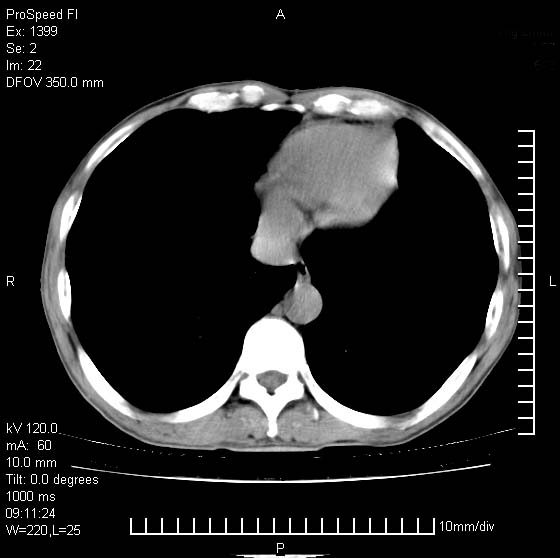

以下是引用卜一在2007-1-19 9:55:00的发言:[br]左肺沿胸膜下巨大肿块影,边缘呈分叶征,纵隔内见肿大淋巴结,右肺内另见一不规则结节影 .考虑:左肺周围性肺癌伴纵隔 右肺内转移.

以下是引用rgsyyf在2007-1-19 11:05:00的发言:[br]左肺上叶见形态不规则巨大软组织肿块影,边缘呈分叶征,纵隔内隆突下见肿大淋巴结,右肺内另见一不规则结节影 .考虑:左肺周围性肺癌伴纵隔即右肺内转移.